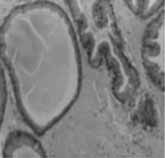

3.3 MT、MT中药复方对角叉菜胶所致前列腺炎大鼠前列腺腺体组织结构的影响(病理切片) 病理报告示:(1)正常对照组:间质内未见炎性细胞及其他异常现象(图1);(2)MT中药复方组:腺泡间质偶见炎性细胞,腺泡排列大小均未见异常(图2);(3)MT组:腺泡间质中可见炎性细胞浸润,结缔组织增生,轻度水肿(图3);(4)模型组:前列腺间质内可见多数炎性细胞浸润,腺上皮可见乳头状增生,结缔组织增生(图4);(5)前列康组:有的腺泡间质内可见炎性细胞,间质疏松,呈水肿状,有的前列腺组织结构基本正常(图5)。

图1 前列腺炎症实验空白对照组

图2 前列腺炎症实验MT+CCTM组

图3 前列腺炎症实验MT组

图4 前列腺炎症实验模型组

图5 前列腺炎症实验前列康组